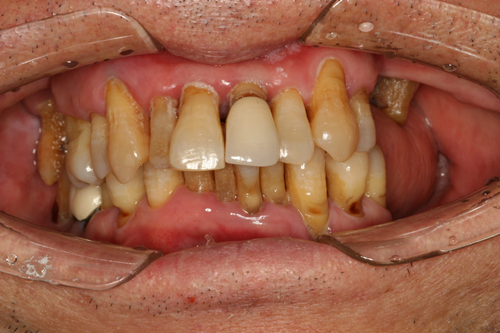

年青时奋斗,老了诸多不便,只想过简单的生活,和朋友一起尝美食、旅游、唱唱歌。我牙口不好,十几年前就安装了假牙,但当时技术、条件并不好,假牙用过几年后就脱落了,后来又查出有晚期牙周炎,经过拔牙、治疗后,仍然没有达到满意的效果,治疗后的牙冠不好用,吃东西塞牙、无味,很是痛苦。

麦芽口腔的郑苍尚院长为我量身定制了"微创无痛数字化口腔种植牙"技术,种牙过程很舒适,就像被蚊子"叮"了一下牙就种好了,全程无痛,种完后也不肿不痛的,相信麦芽就是相信科学。